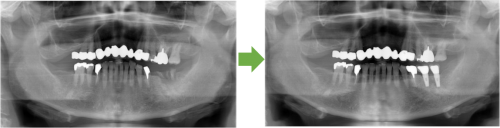

インプラント 抜歯→左下奥歯埋入 川口で精密インプラント治療なら さかえ歯科クリニック「さかえ歯科クリニック」

インプラント 抜歯→左下奥歯埋入 川口で精密インプラント治療なら さかえ歯科クリニック